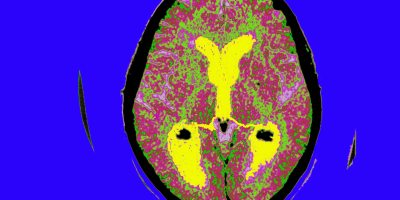

Mid-life inflammation linked to late-life Alzheimer’s